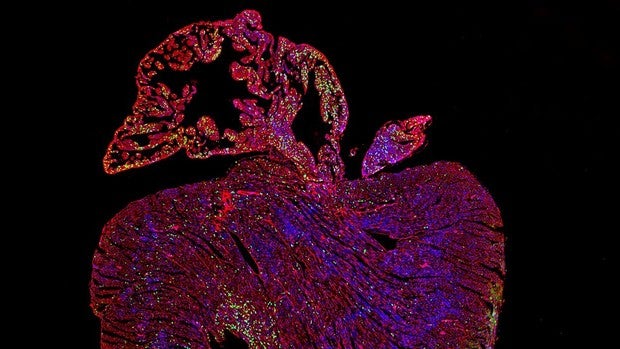

Tratando de desactivar un gen que facilita la propagación del cáncer un equipo de investigadores de la de la Universidad de Cambridge (Reino Unido) han realizado un sorprendente hallazgo. Al hacer que el gen Myc sea hiperactivo y funcional en los corazones de los ratones, han desencadenado la regeneración de las células cardíacas. Debido a que los corazones adultos generalmente no pueden repararse por sí mismos una vez dañados, los científicos creen que aprovechar el poder de este gen representa un gran avance hacia el primer tratamiento curativo para la enfermedad cardíaca. «Esto es realmente emocionante porque desde hace años hemos estado tratando de hacer que las células cardíacas proliferen. Ninguno de los tratamientos actuales para la enfermedad cardíaca puede revertir la degeneración del tejido cardíaco; solo reducen la progresión de la enfermedad. Ahora hemos descubierto una manera de hacerlo en un modelo de ratón», explica Catherine Wilson, investigadora del Departamento de Farmacología de la Universidad de Cambridge, y directora del estudio. El ciclo celular, a través del cual las células hacen copias de sí mismas, está estrictamente controlado en las células de mamíferos. El cáncer se desarrolla cuando las células comienzan a replicarse sin control, y el gen Myc juega un papel clave en el proceso. Se sabe que Myc es hiperactivo en la gran mayoría de los cánceres, por lo que atacar este gen es una de las principales prioridades en la investigación del cáncer. Muchos estudios actuales para el tratamiento del cáncer se han centrado en tratar controlar Myc. Cuando los genes Ccnt1 y Myc se expresan juntos, el corazón cambia a un estado regenerativo y sus células comienzan a replicarse. En el estudio que ahora se publica en «Nature Communications», cuando los investigadores hicieron que Myc fuera hiperactivo en un modelo de ratón y, como esperaban, vieron sus efectos cancerosos en órganos como el hígado y los pulmones: una gran cantidad de células comenzaron a replicarse en el transcurso de unos días. Los investigadores descubrieron que la actividad impulsada por Myc en las células del músculo cardíaco depende del nivel de otra proteína llamada Ciclina T1, producida por un gen llamado Ccnt1, dentro de las células. Cuando los genes Ccnt1 y Myc se expresan juntos, el corazón cambia a un estado regenerativo y sus células comienzan a replicarse. «Cuando estos dos genes se sobreexpresaron juntos en las células del músculo cardíaco de ratones adultos, vimos una replicación celular pronunciada, lo que condujo a un gran aumento en la cantidad de células del músculo cardíaco», destaca Wilson. La insuficiencia cardíaca afecta a alrededor de 23 millones de personas en todo el mundo cada año y, actualmente, no hay cura. Después de un infarto, un corazón humano adulto puede perder hasta mil millones de células del músculo cardíaco, llamadas cardiomiocitos. A diferencia de muchos otros órganos del cuerpo, el corazón adulto no puede regenerarse, por lo que estas células nunca se reemplazan. Su pérdida reduce la fuerza del corazón y provoca la formación de cicatrices, insuficiencia cardíaca y, en última instancia, la muerte. «Ninguna de las opciones de tratamiento actuales puede revertir la degeneración del tejido cardíaco. La incapacidad del corazón para regenerarse es una necesidad clínica insatisfecha importante», afirma Wilson. Queremos utilizar tecnologías intercambiables a corto plazo para activar Myc y Cyclin T1 en el corazón. De esa forma no dejaremos ninguna huella genética que pueda promover la formación de cáncer En este estudio, añade, «descubrimos que incluso cuando Myc se enciende en un corazón, las otras herramientas no están ahí para que funcione, lo que puede ser una de las razones por las que el cáncer de corazón es tan extremadamente raro. Ahora sabemos lo que falta, podemos agregarlo y hacer que las células se repliquen». Los investigadores esperan desarrollar su hallazgo en una terapia genética para el tratamiento de enfermedades del corazón. «Queremos utilizar tecnologías intercambiables a corto plazo para activar Myc y Cyclin T1 en el corazón. De esa forma no dejaremos ninguna huella genética que pueda promover la formación de cáncer», dijo Wilson.Fuente Salud https://ift.tt/3enwake